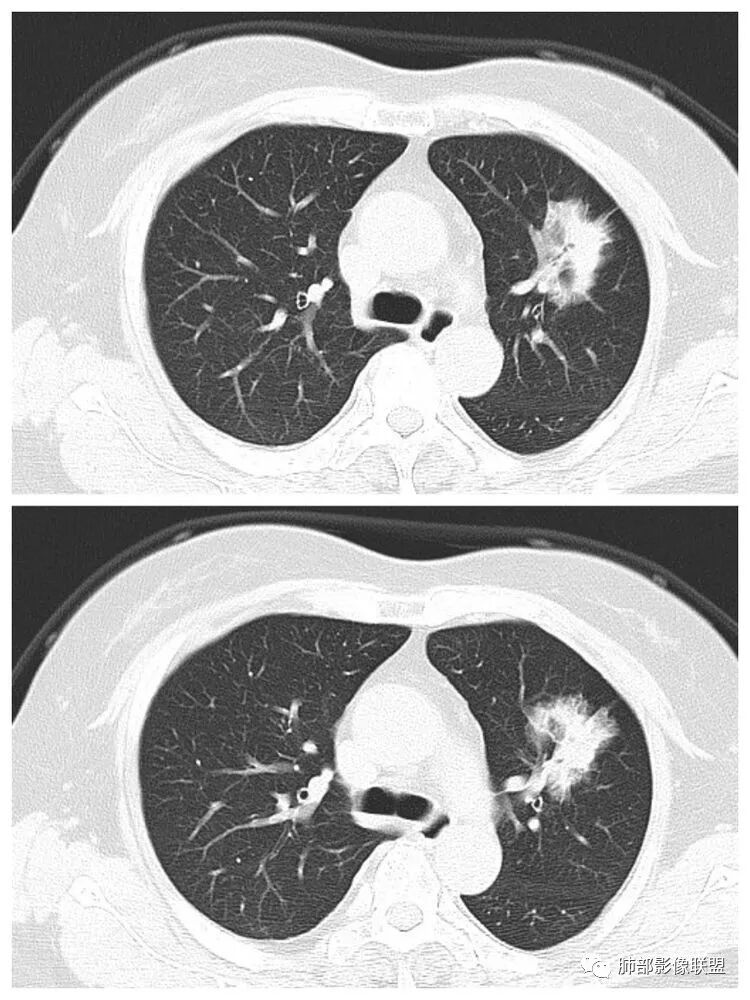

以下是两个时间点左右对比

2019.11.26  👇                           2020.01.20👇                                            2019.11.26片

2020.01.20片

2.早期CT表现左肺上叶不规则团块影,呈混合密度,以实性密度为主,但整体密度偏低,周围隐约见磨玻璃密度影。

边缘不规则,前内侧缘见小叶间隔限制(注意,并非典型深分叶),病灶外侧细长毛刺,病灶内有小空泡及空气支气管征,有胸膜牵拉征象。

上述征象均提示病灶为恶性病灶,但边缘特征及空气支气管征似乎有别于常见的浸润性腺癌及MALT。

3.复查影像显示病灶整体大小变化不明显,其内空泡消失,但是周围磨玻璃影趋于似清非清,整体病灶收缩力中等偏弱,均提示粘液腺癌的可能性大。